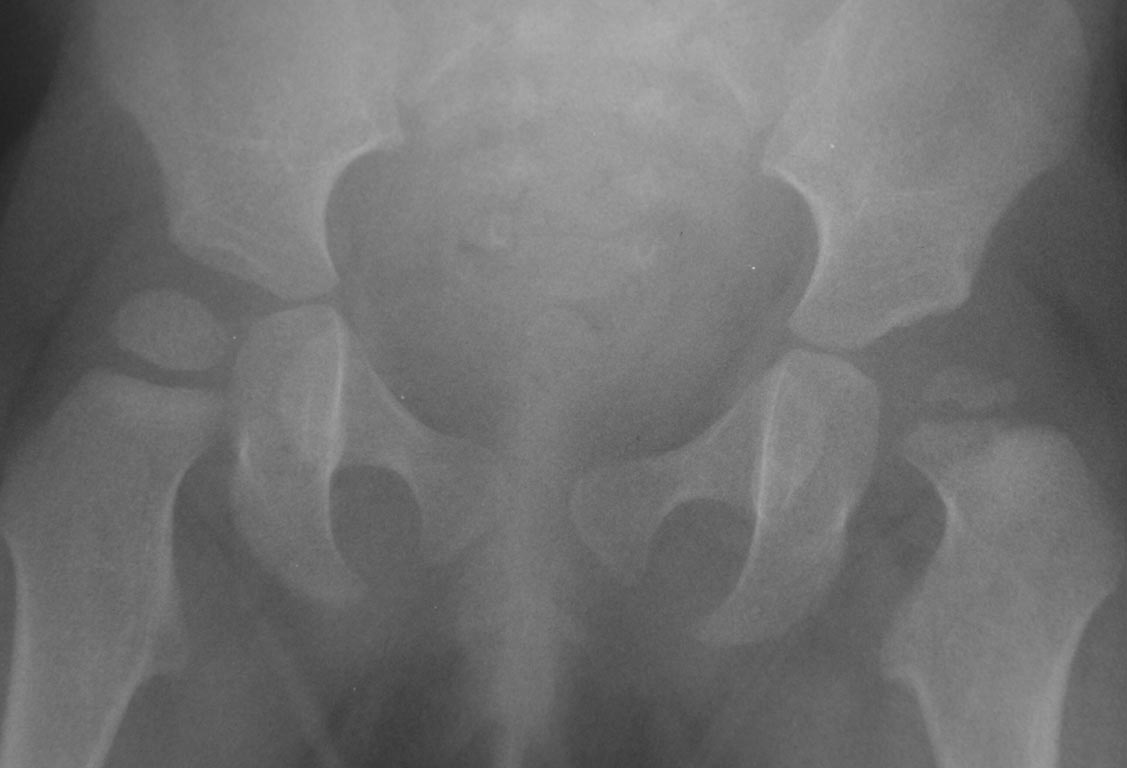

Добрый вечер уважаемые коллеги. Помогите советом, в какую клинику и к

кому обратится с данной проблемой( у ребенка в возрасте 1мес.

диагностирован гематогенный остеомиелит головки бедра). Лечили

консервативно( выписку и фото в динамике прилагаю). На сегодняшний день

ребенку 11 мес. Детские ортопеды по месту сомневаются в тактике( в плане

операции или выжидательная тактика). Хотелось проконсультироваться с

теми кто занимается этой проблемой. Заранее спасибо.